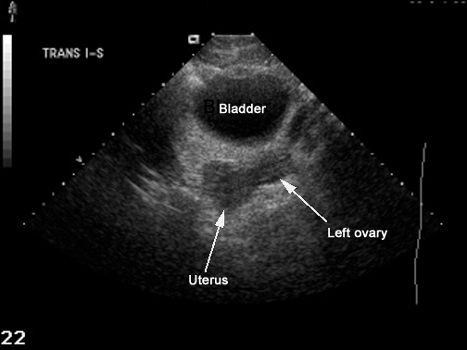

US Pelvis |

|